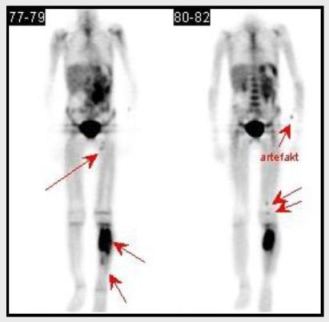

2. pacient

Osmiletý chlapec přicházející pro zhoubný

novotvar kosti, na PET/CT prokázána patologická ložiska levé tibie

proximálně i distálně, dále měkké tkáně v oblasti politeální jamky

a levého stehna se zobrazením lymfonodů.